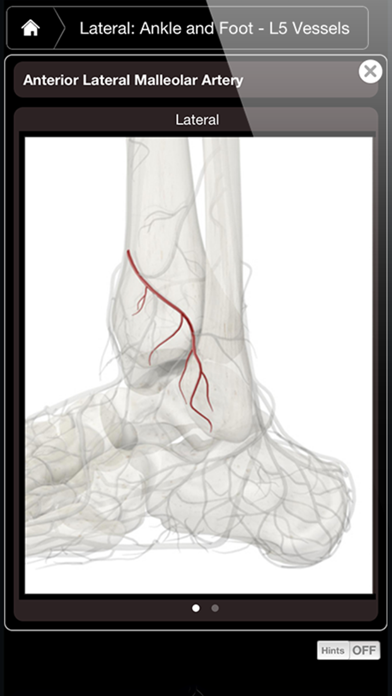

1. Ankle & Foot Pro III provides multiple cross sections (Sagittal, Coronal and Transverse) as well as the ability to cut away different layers revealing the muscles, blood vessels, nerves and connective tissue down to the skeleton.

2. • Multiple 3D cross sections (Sagittal, Coronal, and Transverse) and the ability to cut away different layers down to the bone.

7. • Each cross section shows muscle, nervous, vascular and skeletal systems with detailed information on each system - with the touch of a pin.

8. Additionally, this app is ideal for physicians, educators, or professionals in helping explain certain conditions, ailments and/or injuries.